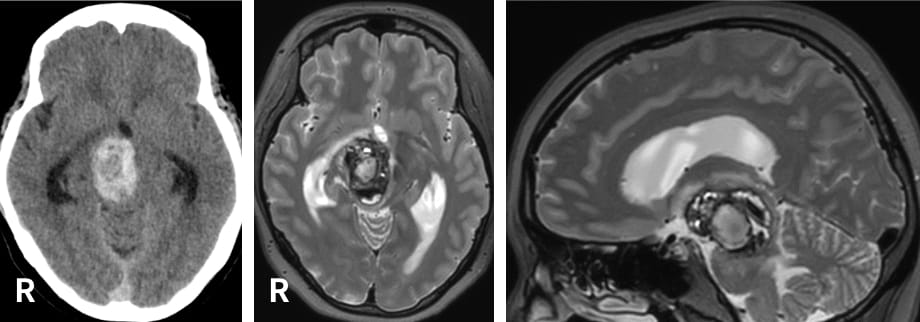

元々は中脳の右腹側(前側)の血管腫で、出血を繰り返した例。

水頭症を伴い、意識障害、眼球運動障害、左麻痺を生じた。手術前に入念にシミュレーションを行い、右側の頬骨と眼窩縁を外してのアプローチにより、大部分の摘出がなされた。

手術後、水頭症は消失し、現在までのところは再出血はなく、ADL(日常生活動作)自立となった。

術前

術後